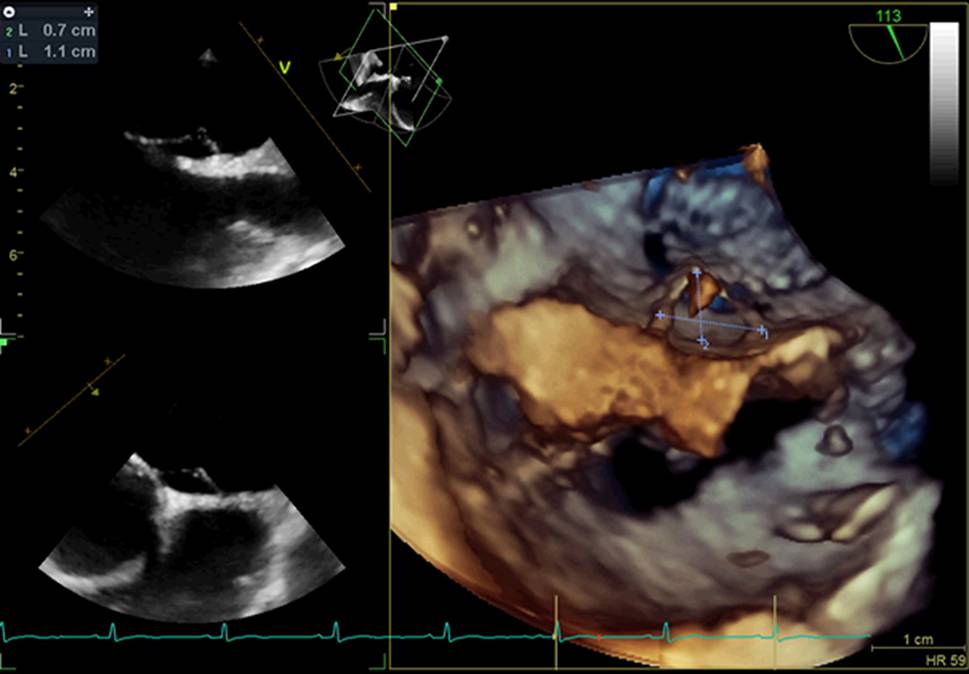

As described in the PASCAL score, a risk-enhancing feature was defined as a Grade 3 shunt or higher and/or an ASA with at least 10 mm of excursion from midline (see Fig. 4; [10]).

Fig. 4

TTE image of a mobile ASA with an excursion of more than 15 mm